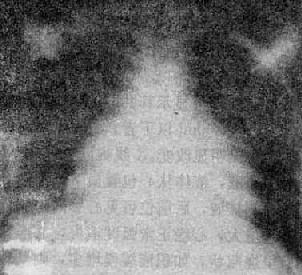

X线表现(图3-2-19)为:①心影大小正常或轻度增大,也可中度增大,增大的原因为心包增厚、心包腔内少量积液或心室舒张障碍,使右心房压力升高而出现右心房增大;②心包增厚粘连使两侧或一侧心缘变直,各弓影分界不清,心外形常呈三角形或近似三角形,亦可呈球或其他形状,有时由于右心房增大,使心右缘呈一个大弧,而心左缘则平直;③心搏动一般明显减弱或消失,但在心包增厚不显著的部位,心可局部膨大,搏动明显增强;④心包钙化是缩窄性心包炎的特征性表现,国内资料占缩窄性心包炎的1.23%~1.56%。钙化可呈蛋壳状、带状、斑片状或结节状等。钙化多分布于房室沟、右心房室的周围、右心室的胸骨面及膈面等处。其次为左心室除心尖以外的部位。一般,钙化不易在后前位上发现,切线位用高千伏摄影最有效,可选择侧位或斜位投照;⑤由于静脉压升高,而使上腔静脉扩张;⑥左心房压力增高时,出现肺瘀血现象;⑦胸膜增厚、粘连。

图3-2-19 缩窄性心包炎

心影增大,心右缘呈一个大弧,心左缘各弧分界不清,

未见钙化,肺纹理增多